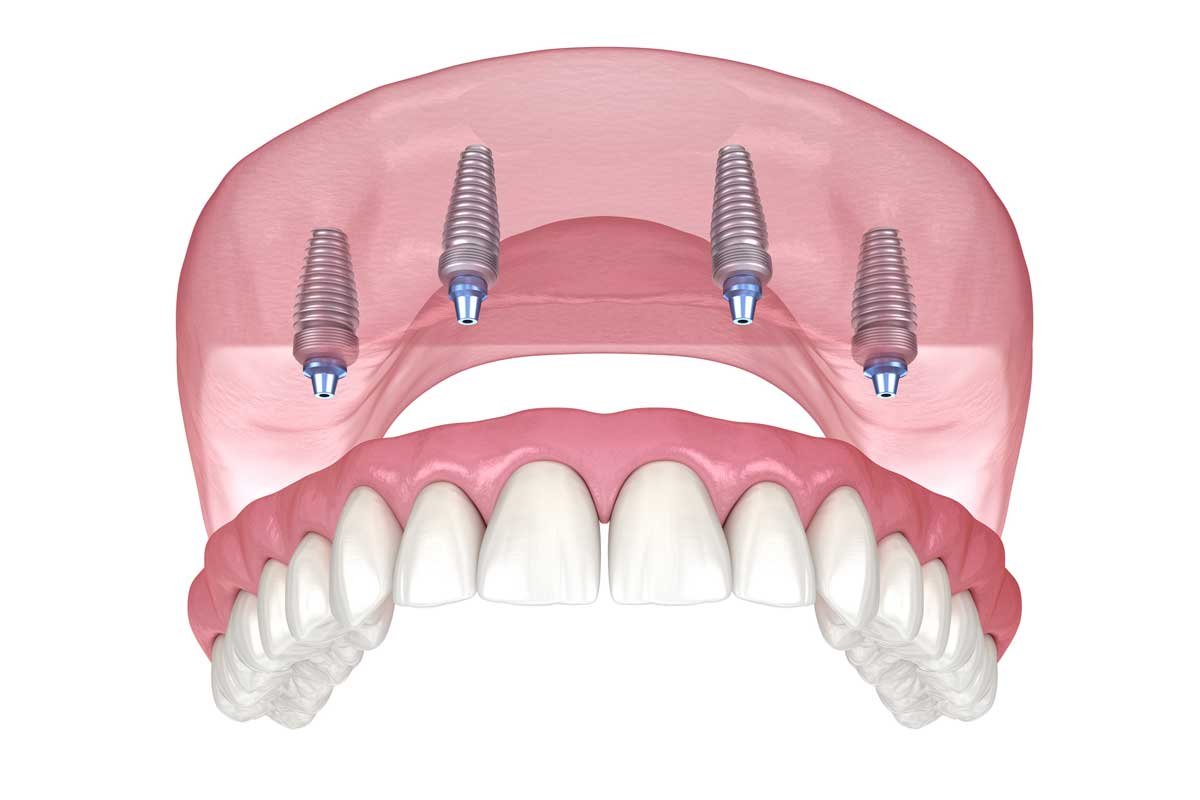

All-on-4

Solução para arcada total com quatro implantes estrategicamente inclinados, reduzindo necessidade de enxertos. Pode receber carga imediata quando critérios técnicos são atendidos.